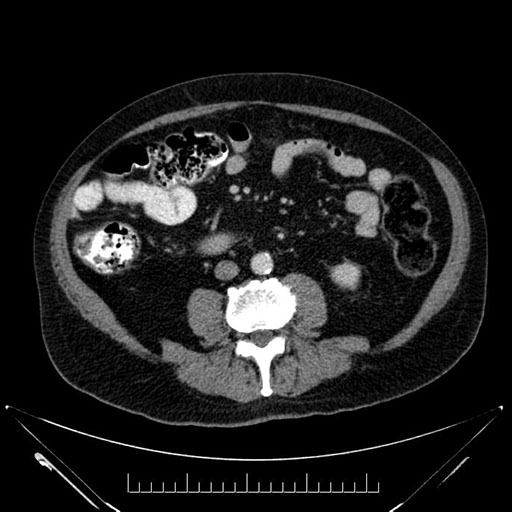

Whipple (pancreaticoduodenectomy) [case 7]

Imaging Analysis

Look through the patient's CT scan to identify any areas of concern for the necessary procedure.

Axial - 3 months prior